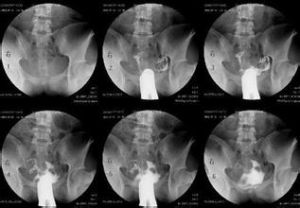

陰道平滑肌肉瘤的治療中採用區域動脈灌注化療,可以提高局部組織的藥物濃度和提高療效,且全身毒性較低,局部控制率可達80%。用阿黴素動脈灌注化療,50%腫瘤出現壞死,化療後加用X線放射35Gy,可提高療效。

陰道後壁平滑肌肉瘤局部發展較晚期時,在行後盆內臟切除後,盆底區域加用體外放射,亦可取得較好近期療效。